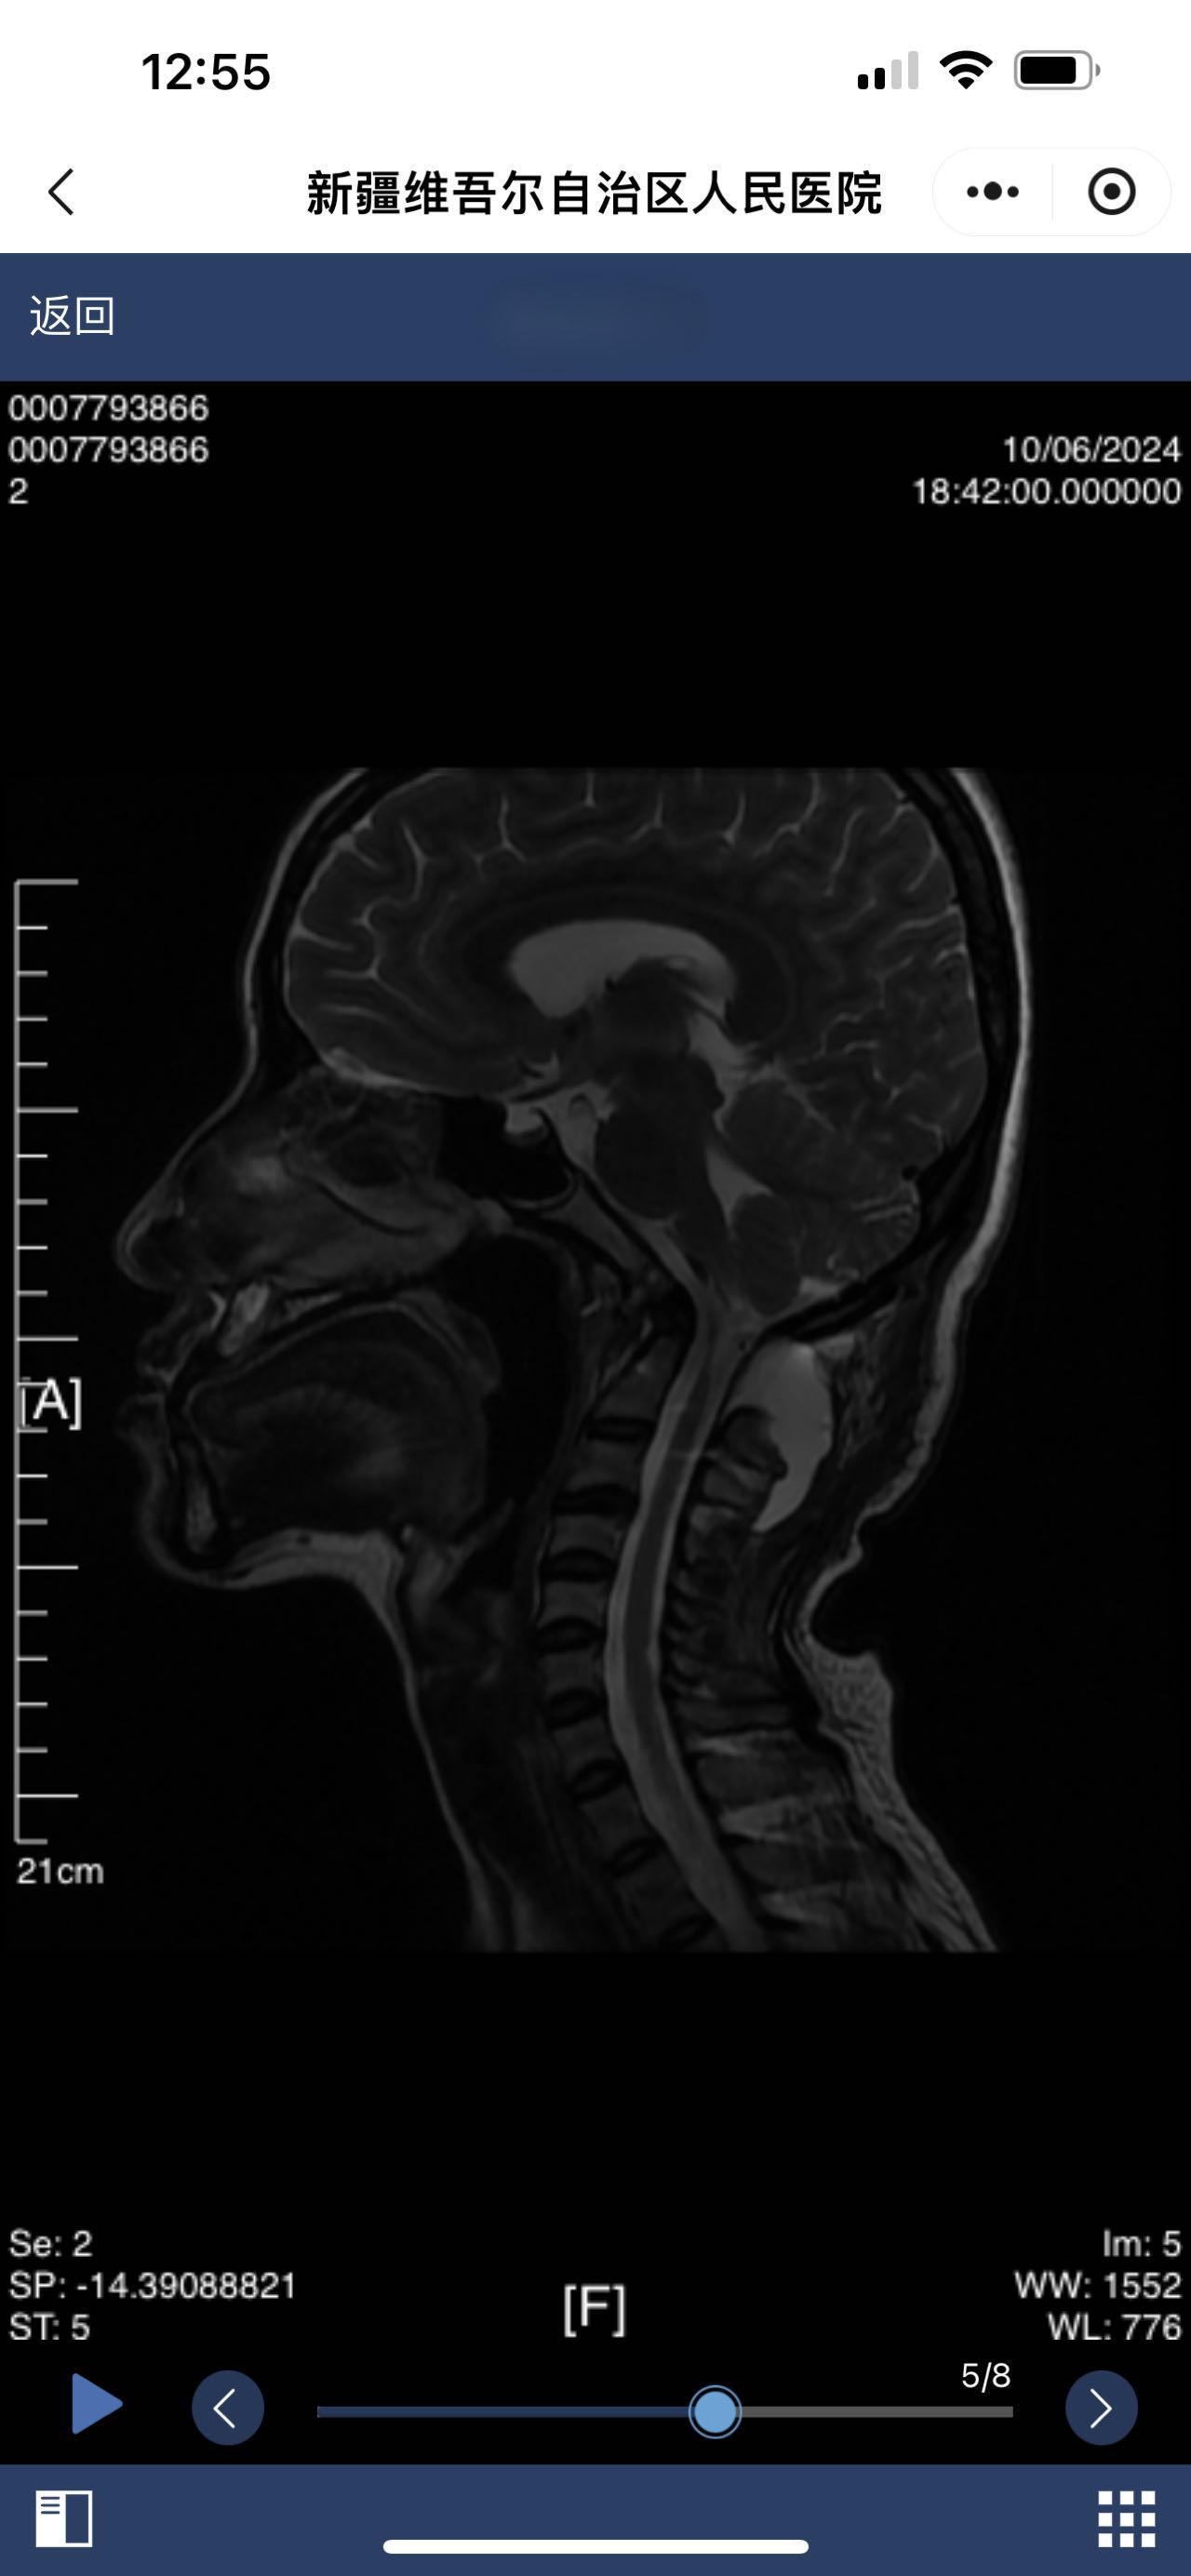

• 诊断:颅底凹陷

• 影像:

• 术后影像:

• 2024.10.06,积液范围略小。